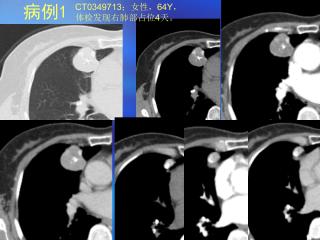

肺部结节的CT鉴别诊断-肺部磨玻璃样病变【90页】

肺部磨玻璃样病变(GGO)是一种非特异性征象病理基础包括肺组织渗出、炎症性间质性增厚、水肿、纤维化及肿瘤组织增生可由感染性疾病、纤维化或肿瘤等引起。常见疾病包括肺肿瘤(细支气管肺泡癌BAC、腺癌、不典型腺瘤样增生AAHP)、局灶性肺间质纤维化FIF、曲菌病等感染性病变、嗜酸性肺炎、阻塞性细支气管炎伴机化性肺炎BOOP等。其中BAC非侵润性腺癌NGGO代表肿瘤细胞替代正常肺组织;FIF是良性NGGO较长时间无变化;曲菌病常伴实变。鉴别诊断要点包括:病变边缘、大小对NGGO诊断无帮助;短期随访恶性GGO或局灶性肺间质纤维化不缩小;综合临床表现、影像学征象、实验室检查是关键;NGGO伴实变、实验室检查阳性应高度怀疑腺癌或BAC;NGGO伴临床症状应考虑炎性NGGO。